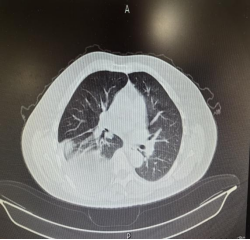

入院后完善胸部CT

结果显示右侧巨大膈疝(膈膨升?),右肾、胆囊、胃窦等多个腹腔器官都通过膈肌的“蓬松”缺损疝入胸腔,还压迫得右肺体积缩小、纵隔左移。为确保治疗万无一失,科室迅速组织心胸外科、呼吸内科、放射影像科、心血管内科、ICU、麻醉科等多科会诊,最终敲定手术方案。